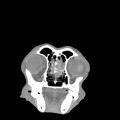

CT - lebka